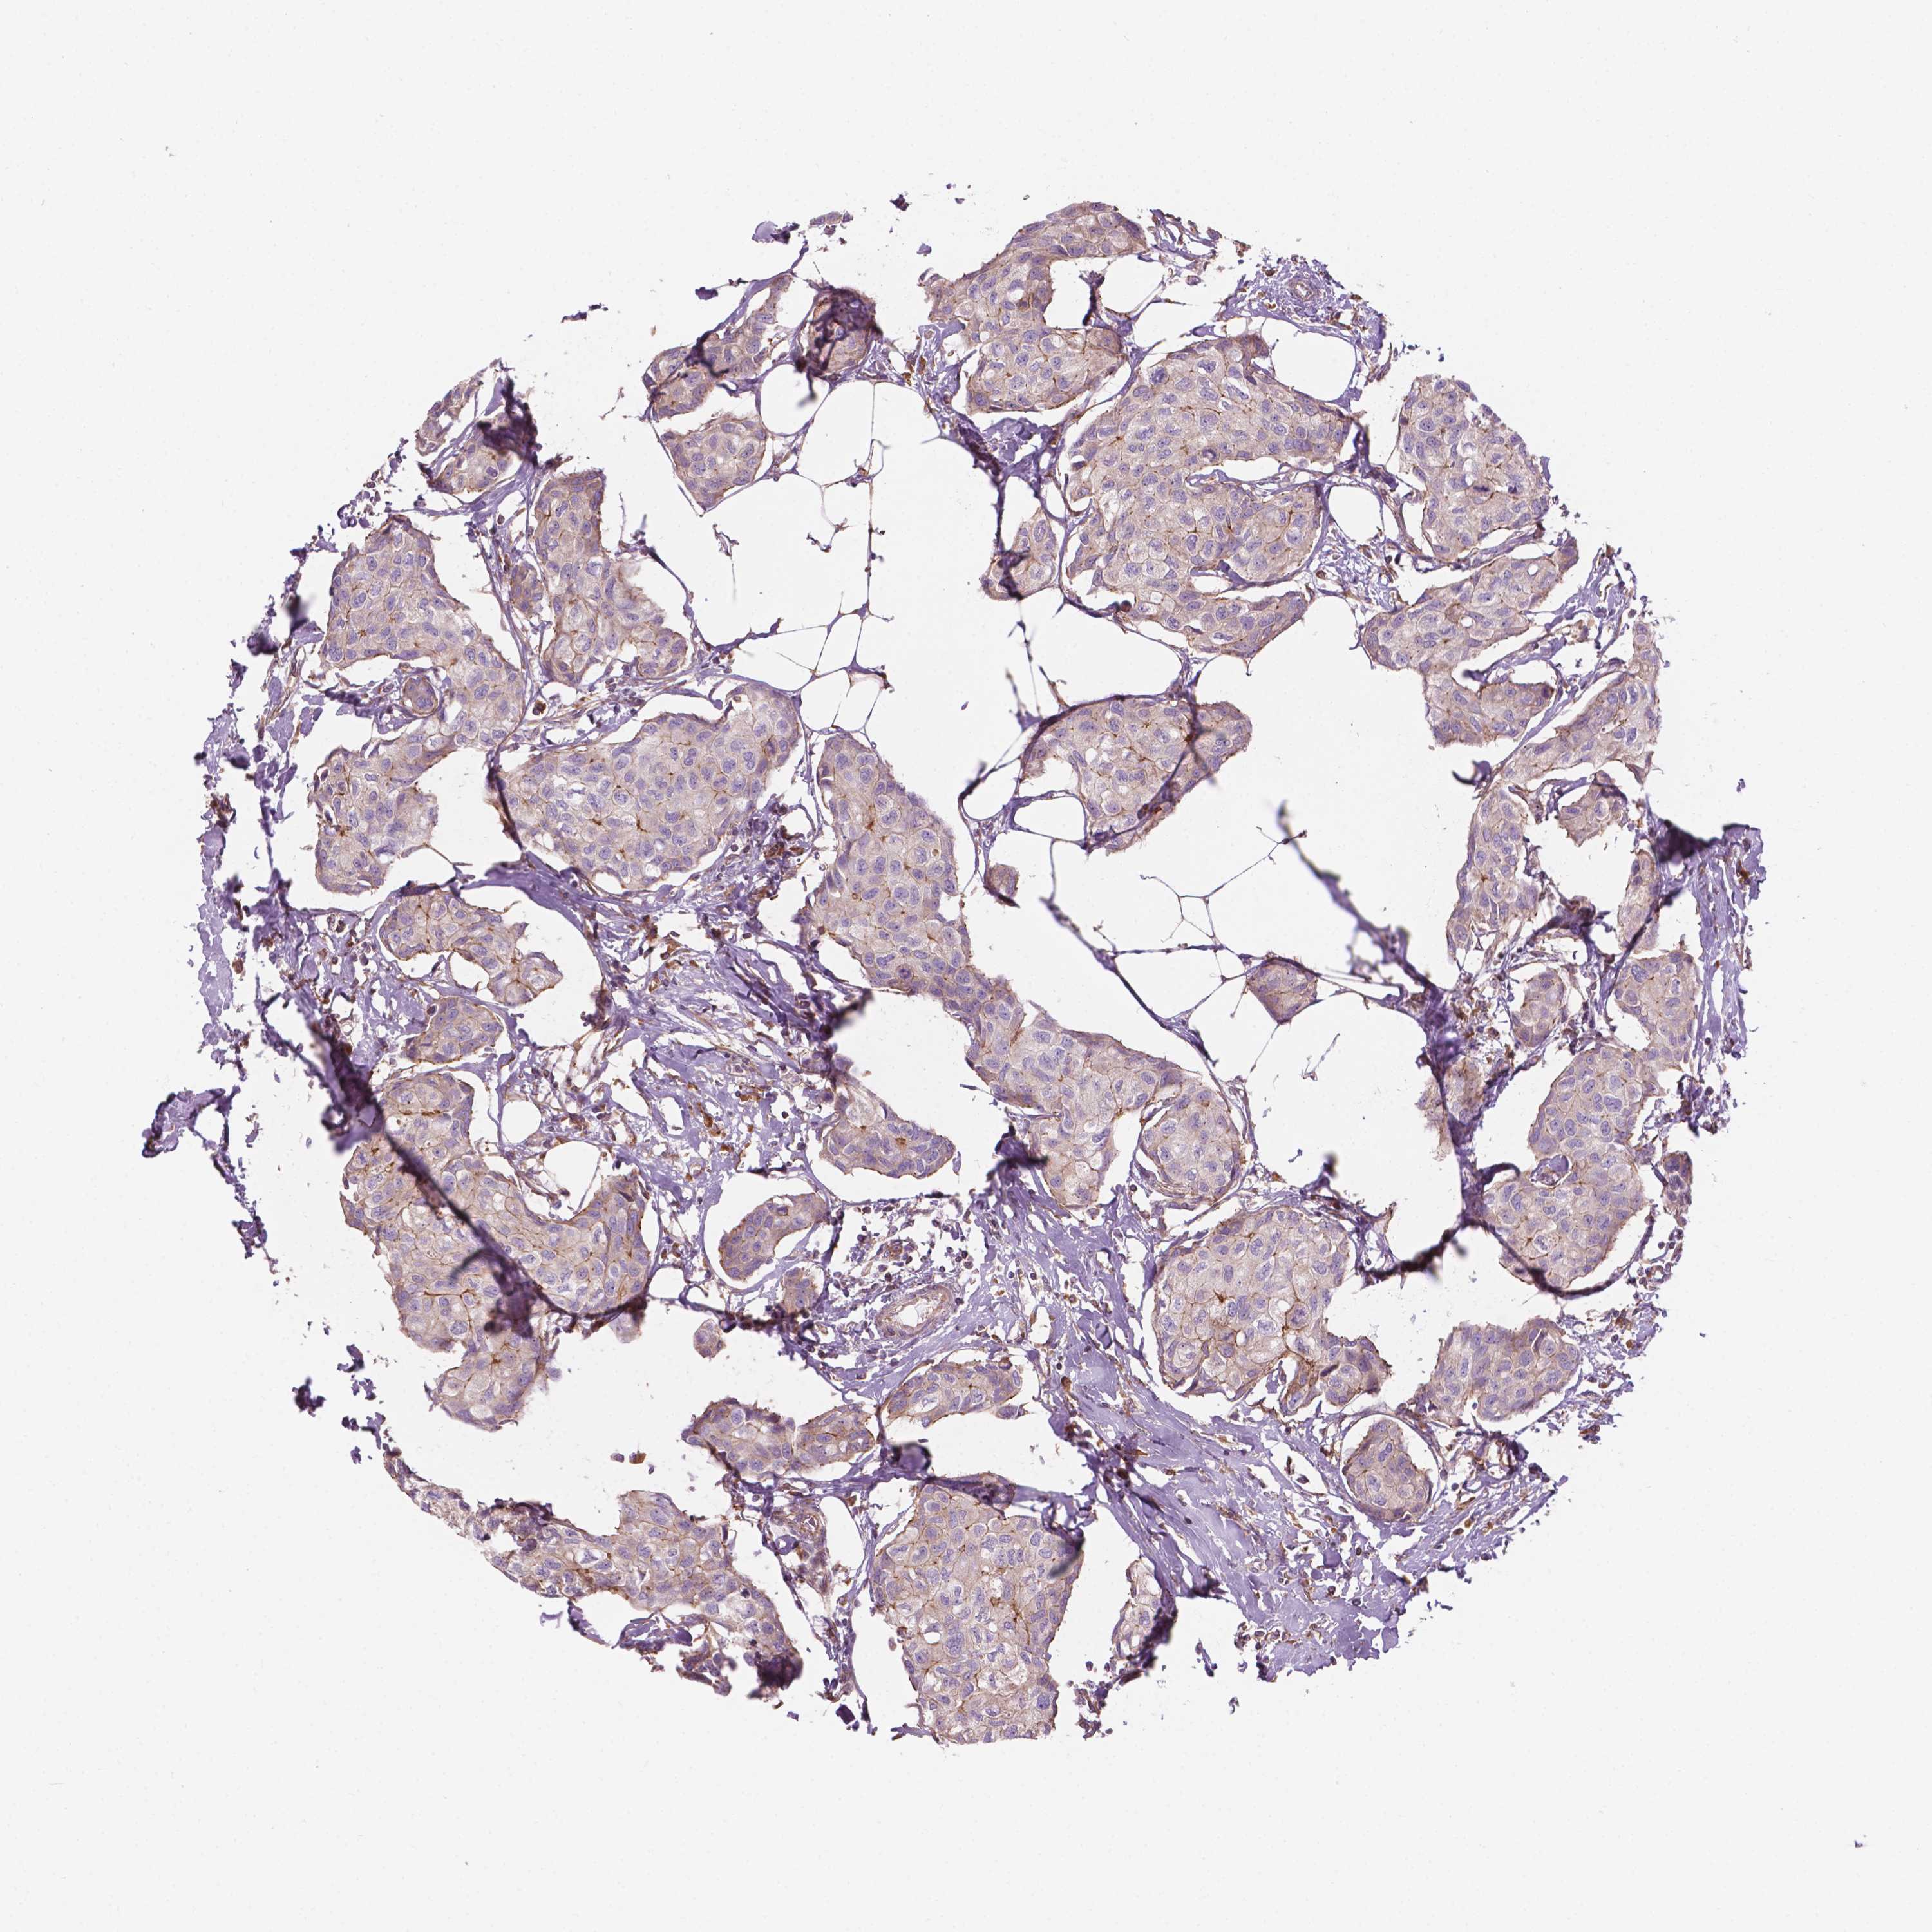

BRCA TCGA BRCA VALIDATION PROTEIN EXPRESSION

ANTIBODIES

AND

VALIDATION